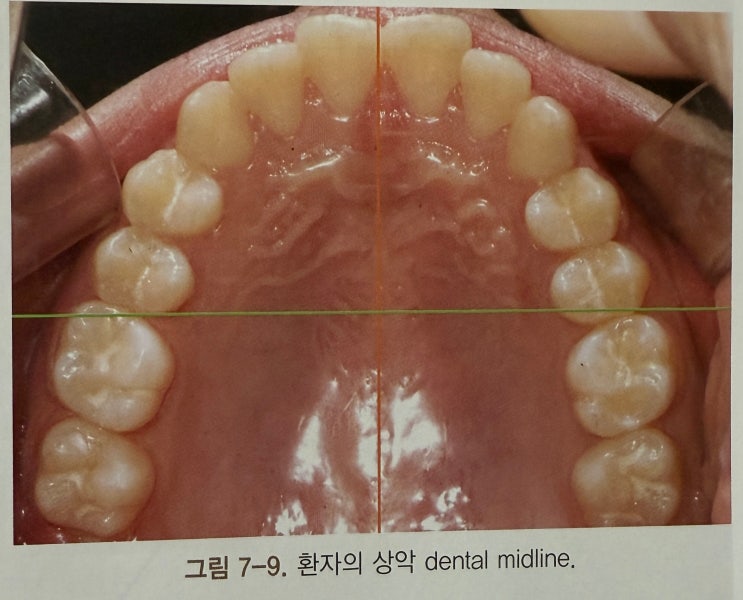

[치과임상책] 평생수제자 교정치료바이블 _ 7장 (Count down to retention)

드디어 Finishing 과정이 마무리 되었다. 꽤나 긴 여정이었지만 교정치료의 진수이기 때문에 찬찬히 읽어...

드디어 대망의 단원, 6장 피니싱이다. 공간폐쇄를 마무리 했으면 시작되는 피니싱단계는 사실상 교정치료의...